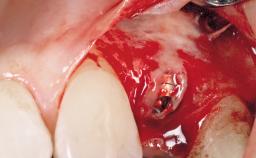

Soft Tissue Grafting Simultaneous

Placement Protocol Immediate implant placement

Socket Integrity Damage to one or more bone walls

Bone Volume Damage to one or more socket walls